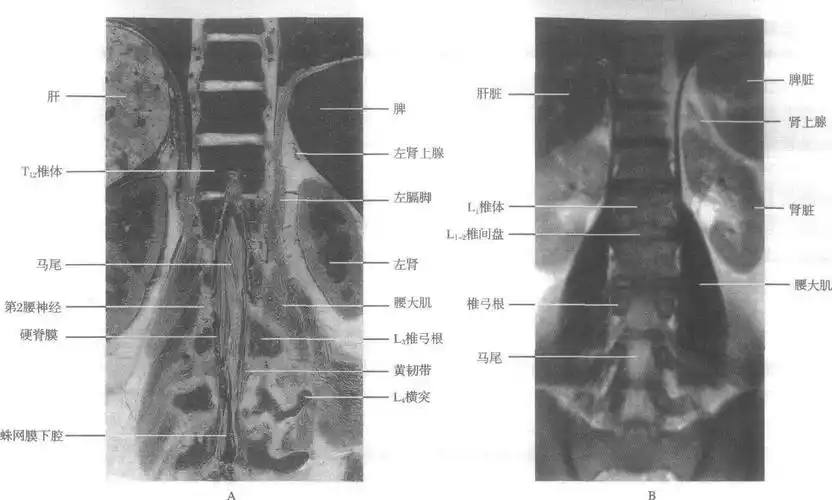

第三节腰椎的mri解剖